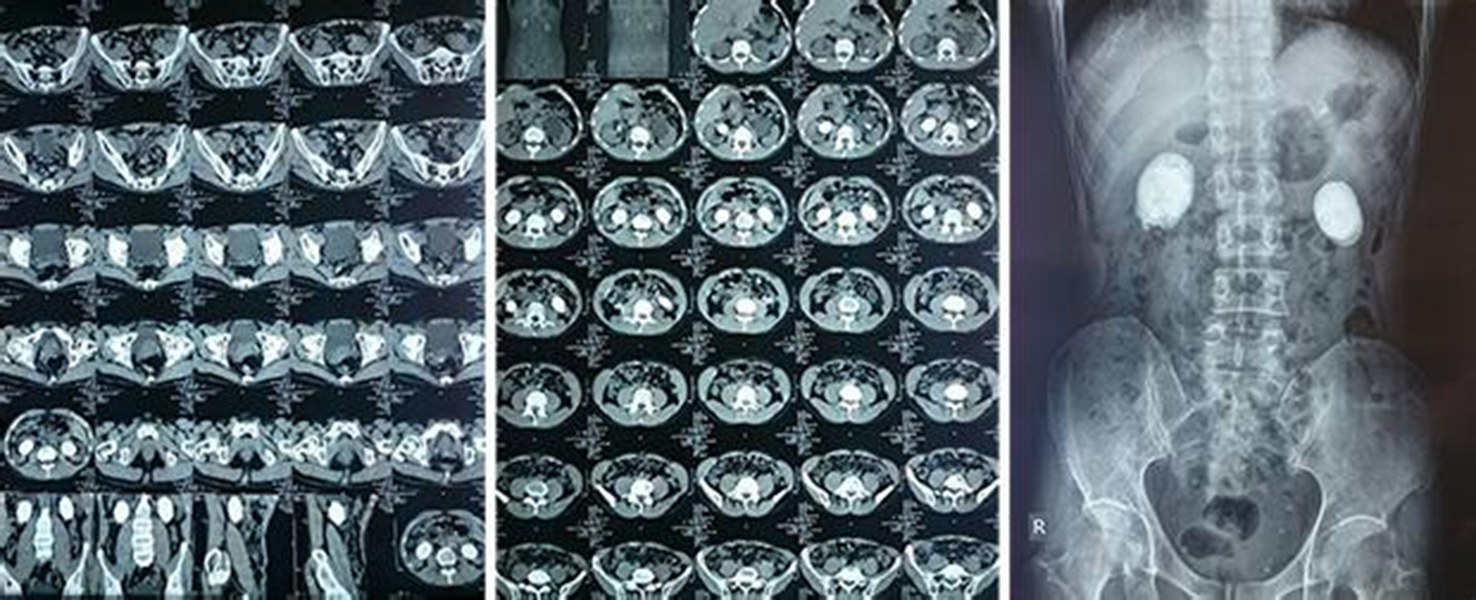

X線、B超、CT檢查

腎結石CT2

腎結石CT3